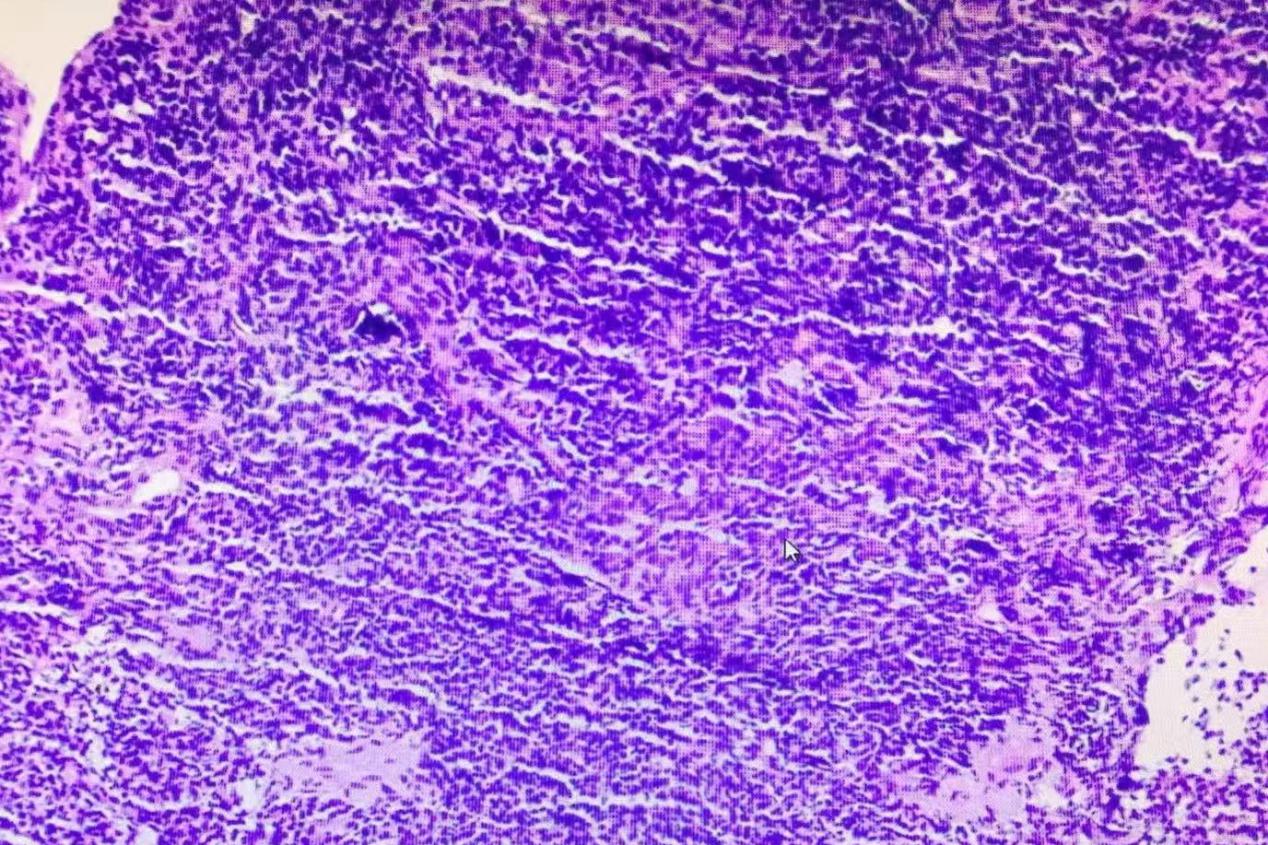

病理科结合患者的CT表现以及肺冷冻活检的取材部位与免疫组化结果,对活检组织进行了详细分析,最终确诊为一种罕见的肺淋巴瘤,即“肺黏膜相关淋巴组织结外边缘区淋巴瘤”(简称为MALT淋巴瘤)。MALT淋巴瘤是一种低度恶性的B细胞非霍奇金淋巴瘤,临床表现不典型,早期症状轻微,影像学表现多样且缺乏特异性,因此极易误诊。常规支气管镜下使用普通活检钳取出的组织样本量,往往难以满足确定病理诊断的需要,导致明确诊断困难。

▲病理切片图像,显示MALT淋巴瘤的典型病理特征